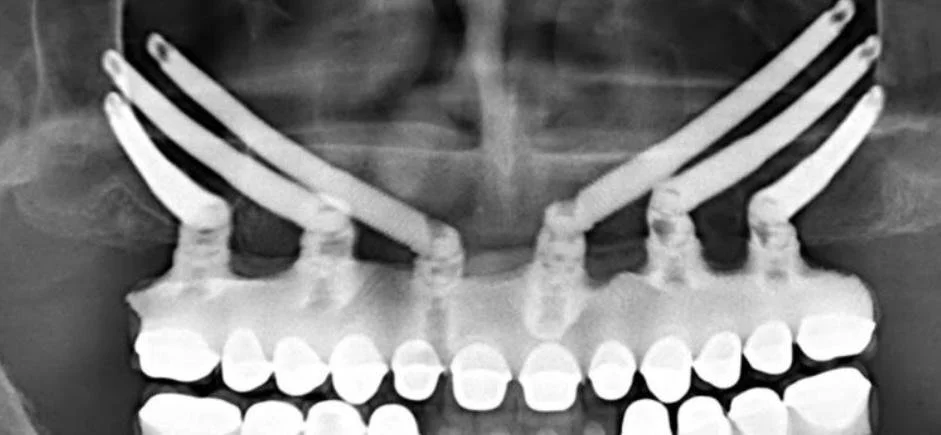

PMMA - While in the dental office you may hear the abbreviation PMMA used. PMMA or Poly (methyl methacrylate) is a rigid, transparent, synthetic plastic also known as acrylic (it is another way to say acrylic). The picture to the right is of a PMMA All on 6, but PMMA is also used to make regular dentures.